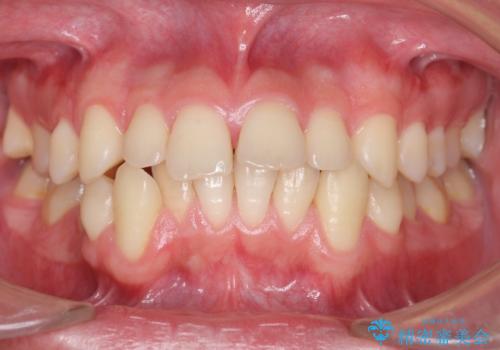

- 前歯の並びをきにして来院。

歯を抜かずに、やすりがけすることでスペースを獲得し、前歯をしっかり下げました。

また、インビザラインに先駆けて、右下はワイヤーによる部分矯正を行い、犬歯をしっかり後ろに下げました。

下げる時に、矯正用ミニスクリューを使用しています。